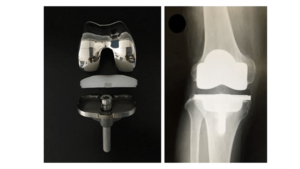

Read MoreMISCR Knee Replacement – Minimally Invasive, Maximally Effective

MISCR Knee Replacement – Minimally Invasive, Maximally Effective Minimally Invasive...